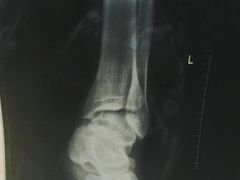

• 中国人民解放军总医院

• -中国人民解放军总医院